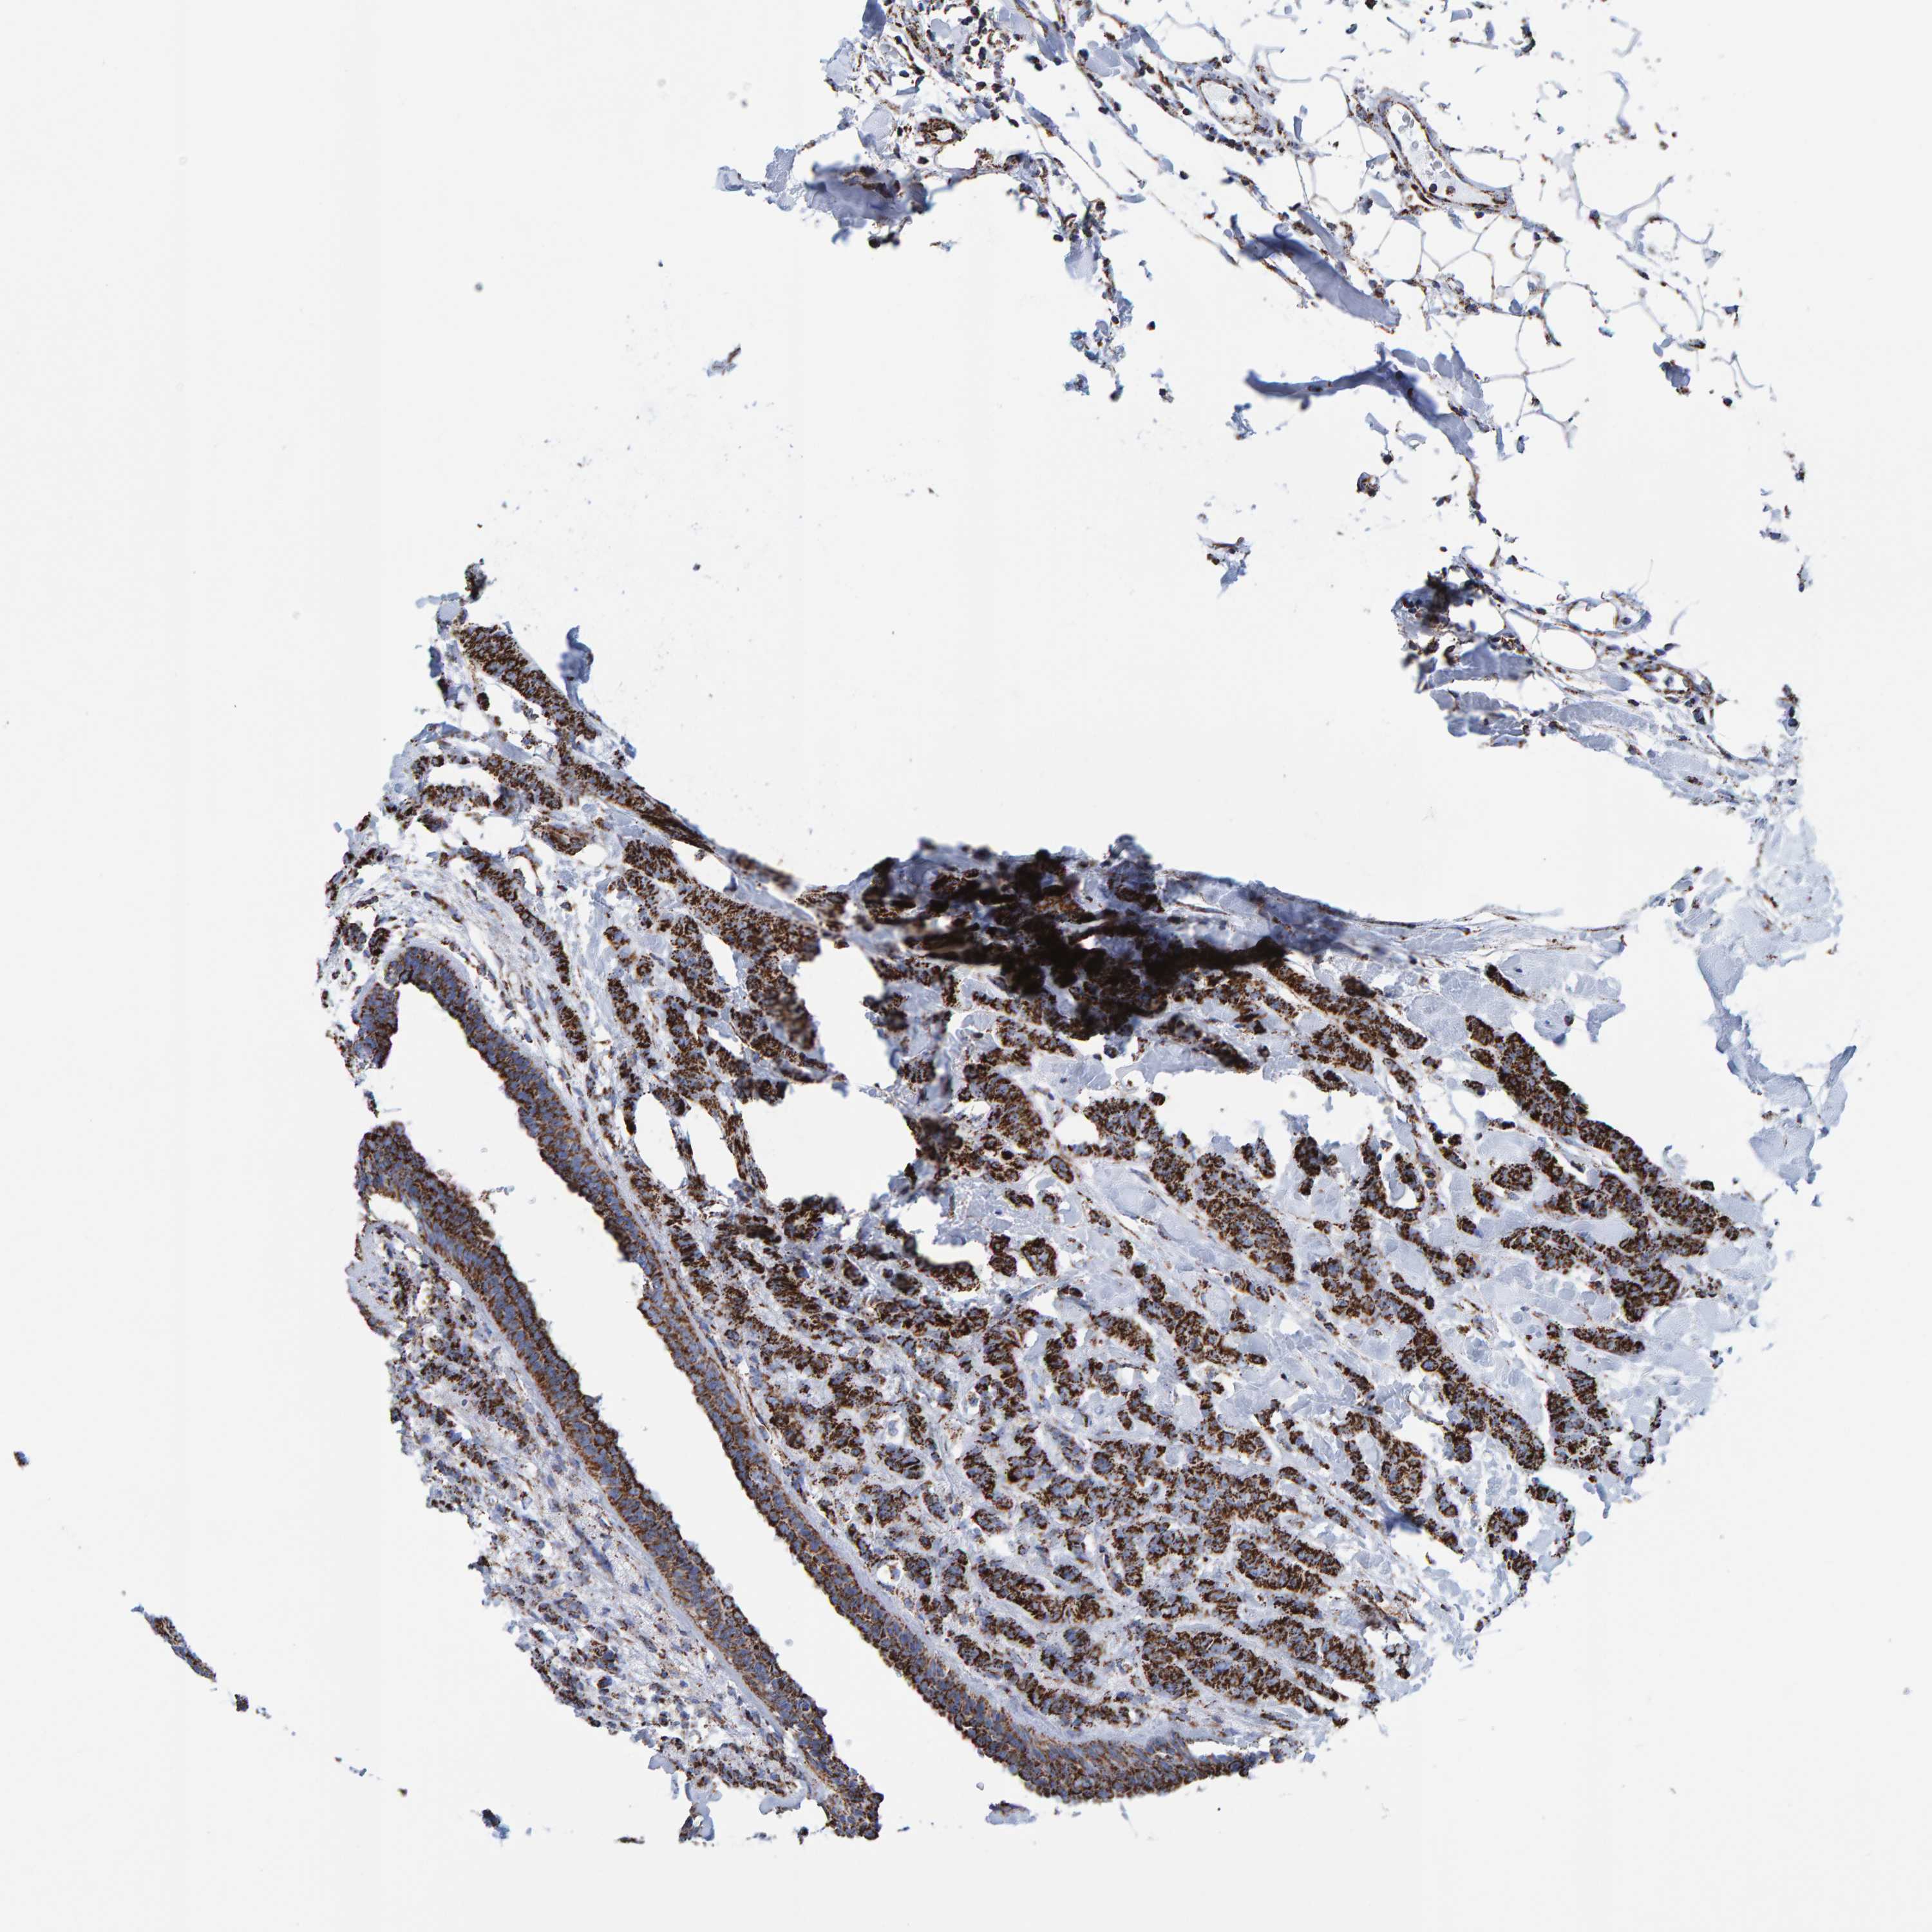

CANCER BREAST CANCER Show tissue menu

BRCA TCGA BRCA VALIDATION PROTEIN EXPRESSION